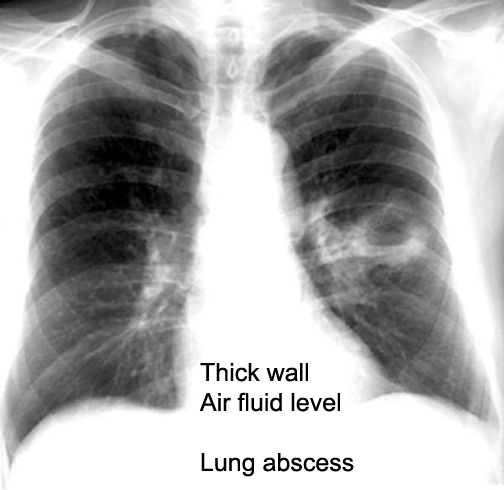

Case 20 Labeled Image List organisms causing necrotizing pneumonia leading to cavitation.